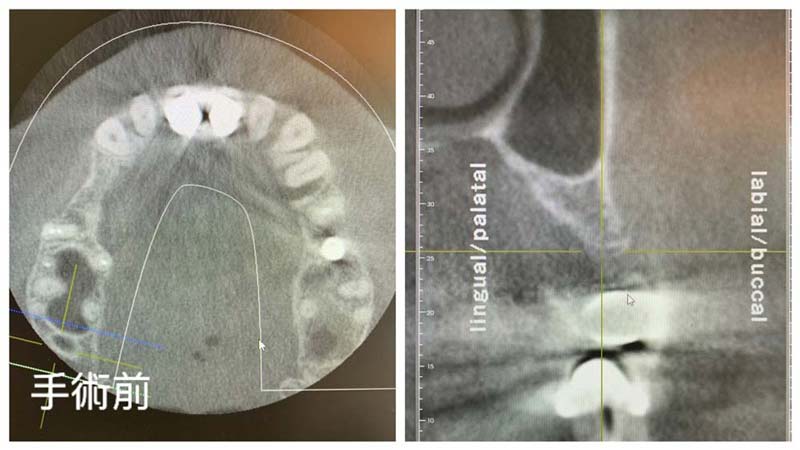

以人工骨粉及人工再生膜施作之齒槽骨再生術,能有效回復齒槽骨厚度,以保障後續植牙治療能建立在高品質的地基上